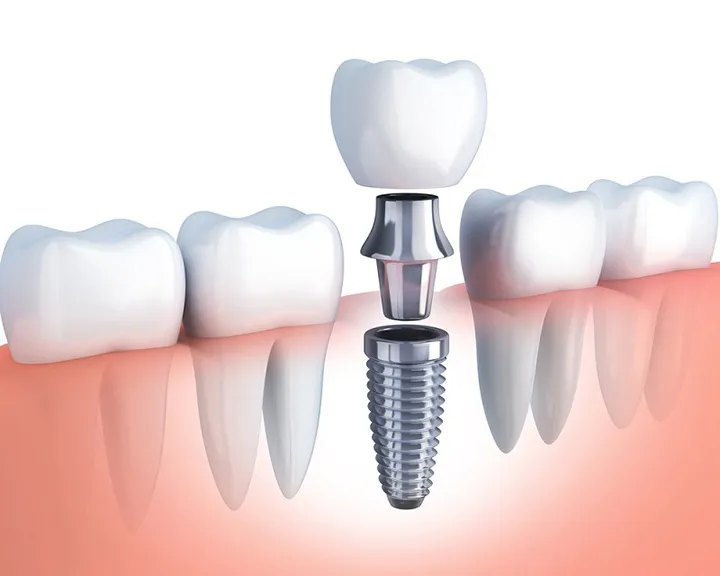

Để tối ưu hóa kết quả điều chỉnh nụ cười tại Hải Phòng, các nha khoa uy tín thường kết hợp thêm nhiều kỹ thuật hỗ trợ nhằm mang lại tính thẩm mỹ và chức năng tốt nhất. Với những trường hợp răng chỉ xỉn màu nhẹ, tẩy trắng răng công nghệ cao là giải pháp nhanh chóng và hiệu quả để cải thiện màu sắc tổng thể của nụ cười. Trám răng thẩm mỹ bằng Composite được ứng dụng để đóng các kẽ thưa nhỏ hoặc phục hồi những phần răng sứt mẻ nhẹ, giúp hàm răng đều và tự nhiên hơn mà không cần can thiệp quá sâu. Trong trường hợp thiếu răng, cấy ghép Implant được thực hiện nhằm phục hồi răng mất và đảm bảo sự đầy đủ trên cung hàm trước khi bước vào các giai đoạn thẩm mỹ tiếp theo. Sự kết hợp linh hoạt, đúng kỹ thuật và được thực hiện bởi đội ngũ chuyên môn cao chính là chìa khóa để kiến tạo một nụ cười vừa đẹp, vừa khỏe mạnh theo thời gian.